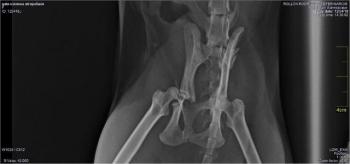

Bijou fand Josefina am Straßenrand. Ein Auto hatte sie erfasst. Das war an einem Sonntagabend. Josefina hat die Maus vorsichtig aufgehoben und gleich am Folgetag zu den Tierärzten gebracht, die bereits Klein-Leo nach seinem Autounfall erfolgreich operiert hatten. Dort wurden sofort Röntgenaufnahmen angefertigt, und es wurde schnell klar, dass Bijou umgehend operiert werden musst. Beide Hüften waren gebrochen. Die rechte Hüfte war nach innen gedrückt. Die Maus muss wahnsinnige Schmerzen gehabt haben. Außerdem drohen bei solchen Verletzungen neurologische Ausfälle. Die Tierärzte gaben die Operationskosten mit 8oo Euro an. Da keine Zeit zu verlieren war, gab Josefina die Zustimmung. Bijou wurde sofort operiert. Die Operation hat mehrere Stunden gedauert. Aber es scheint alles gut verlaufen zu sein. Wie weit sie wieder normal wird laufen können, vermögen wir im Moment allerdings noch nicht zu sagen. Im Moment ist sie in einem Käfig, und soll sich natürlich nicht zu sehr bewegen. In den ersten Tagen nach der Operation hatte Bijou wohl noch starke Schmerzen, so dass sie nicht fressen wollte und gefüttert werden musste. Inzwischen frisst sie wieder und bewegt auch ihre Hinterbeine ein wenig. Bitte alle Daumen drücken, dass die Maus wieder ganz gesund wird!